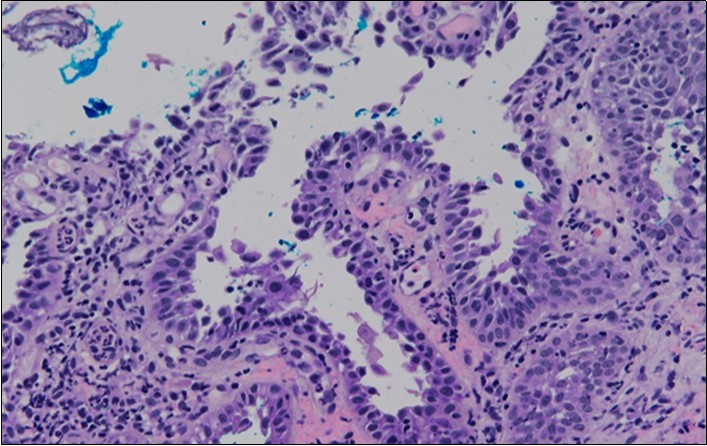

HPV test was negative for high risk subtypes of HPV. The punch biopsy specimen comprised a piece of inflamed cervical tissue in which the transformation zone was represented. The cervical tissue was covered by metaplastic and hyperplastic squamous epithelium showing intraepidermal suprabasal blister formation with acantholysis. Well vascularised dermal papillae lined residual basal cells giving rise to a tombstone appearance were present. There was no evidence of HPV, CIN, CGIN or invasive malignancy.

Figure 4c.Well vascularised dermal papillae with residual basal layer giving rise to tombstone appearance